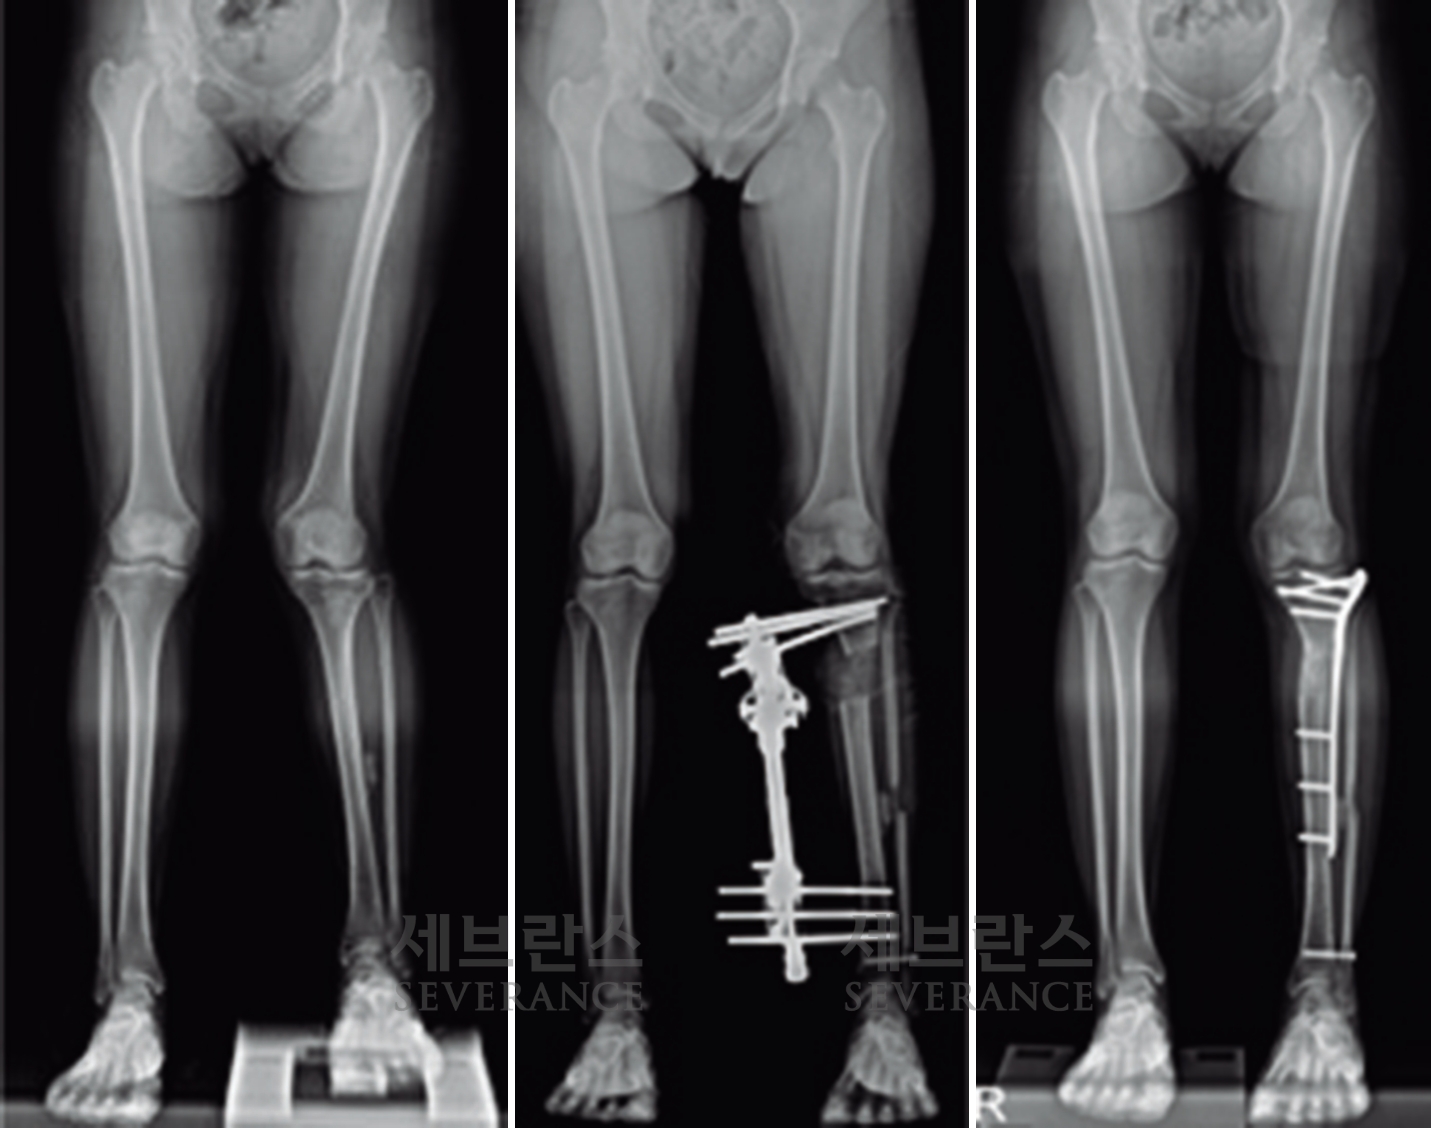

성장판 손상으로 발생한 좌측 외반슬 및 하지부동에 대해 골연장술과 교정술을 동시에 시행해 치료한 환아